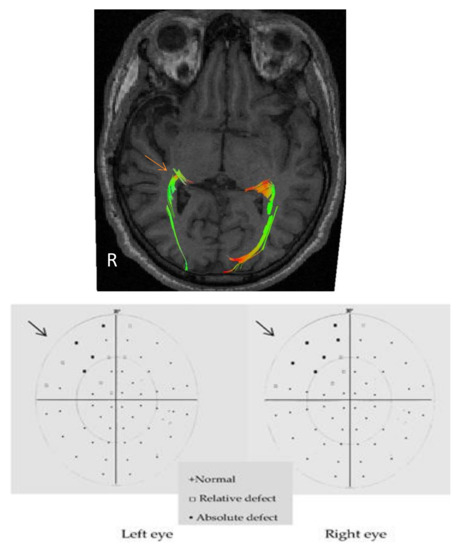

3.2. Visual Pathway

Structure-Function Relationships